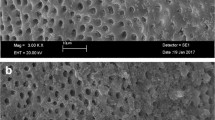

Scanning electron microscopy examination

The teeth were longitudinally grooved, sectioned, and rinsed in phosphate-buffered saline, soaked in glutaraldehyde for 1 h, and then fixed with osmium tetroxide for 30 min [30]. Samples were then dehydrated, mounted on SEM discs, and sputter coated with 5 nm of gold–palladium for conductivity, and examined with a scanning electron microscope (JEOL Model JSM 6010Plus). Representative images were taken of the middle and apical thirds at magnifications of × 500, × 1000, × 5000, and × 10,000.

Scanning electron microscopy analysis

SEM examination shows the presence of bacteria in the dentin tubules in group 1. No bacteria could be visualized in groups 2–5 (Fig. 2). These results may be due to the lower numbers of bacteria in the treatment groups and the limitations of SEM, which include processing of the samples.

The radicular dentin using SEM imaging. The radicular dentin samples were washed and fixed (as stated in the “Materials and methods” section), and then their surface topography was analyzed using scanning electron microscopy (SEM). Bar = 5 μm and × 5000 magnification. Bacteria could be visualized only in group 1, which was the positive control group

Microbiological results were verified with SEM, which showed presence of bacteria in the positive control group but absence of bacteria in the other groups (Fig. 2). Groups G3 and G4 showed positive cultures, but the SEM images did not show the presence of bacteria which could be related to the way these teeth were sectioned and processed and is one of the known drawbacks of SEM imaging [39]. SEM imaging does not help determine the viability of the bacteria and is another drawback of this technique. Hence, CLSM imaging was performed to visualize the presence of live/dead bacteria in the dentinal tubules (Fig. 3).